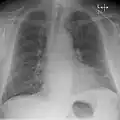

Chest radiograph of a lung with distinct Kerley B lines, as well as an enlarged heart (as shown by an increased cardiothoracic ratio, cephalization of pulmonary veins, and minor pleural effusion as seen for example in the right horizontal fissure. Yet, no obvious lung edema is seen. Overall, this indicates intermediate severity (stage II) heart failure.

Chest X-rays are frequently used to aid in the diagnosis of CHF. In a person who is compensated, this may show cardiomegaly (visible enlargement of the heart), quantified as the cardiothoracic ratio (proportion of the heart size to the chest). In left ventricular failure, evidence may exist of vascular redistribution (upper lobe blood diversion or cephalization), Kerley lines, cuffing of the areas around the bronchi, and interstitial edema. Ultrasound of the lung may also be able to detect Kerley lines.[72]